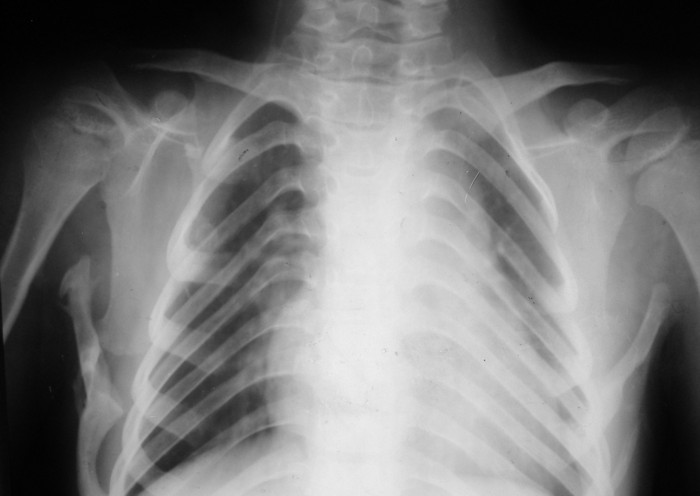

Имя     : chest02.JPG

При инструментальном обследовании выявлено рестриктивный тип нарушения функции легких (крайне резкое снижение), обструктивный тип нарушения функции легких на уровне крупных бронхов (весьма значительное снижение).